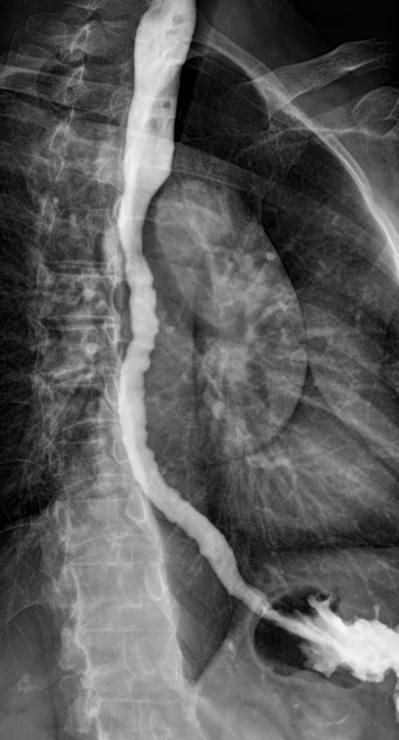

Tertiary Contractions

• Basically a-fib in your throat

• Non-propulsive and un-synchronized contractions of the esophagus

• Can be normal but considered abnormal if triggered by swallowing